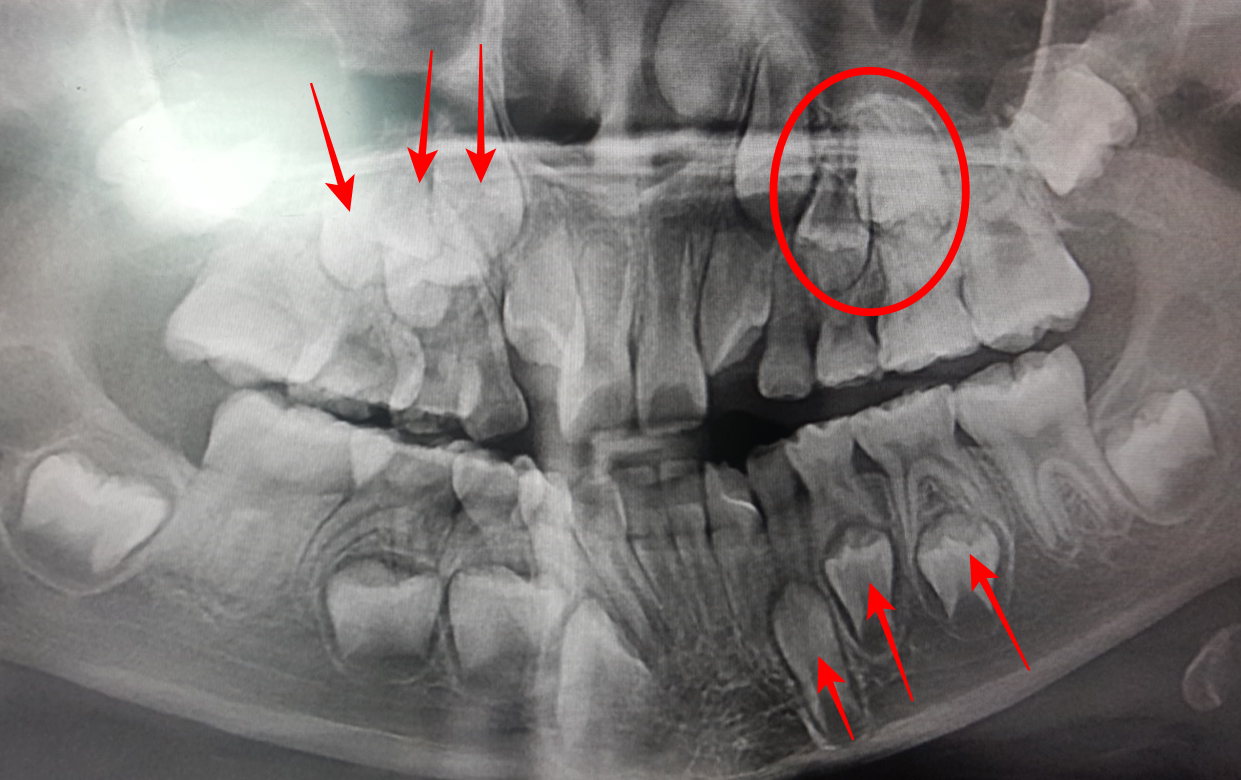

아래 파노라마 엑스레이는 여러분들이 병원에 가실때

자주 찍게 되죠.

파노라마 엑스레이 찍으면

모니터에 띄워놓고 설명할 거예요..

이때 내 아이 치아 사진을 핸드폰으로 찍으세요.

그럼 다음번 빠질 치아를 예측할 수 있습니다.

아래 사진은 8살때 봄이 이빨을 찍은 사진인데요.

엑스레이를 보면 아래 사진과 같이 이번에는 어떤 이빨이 흔들리겠구나 알 수 있습니다.